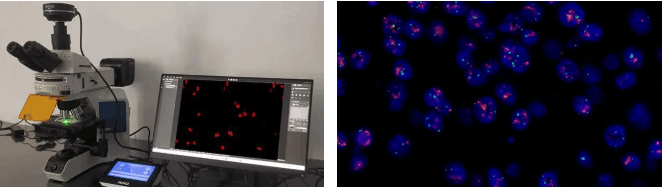

ͨß^Ã÷ÃĀML51-NÉúÎīī@ÎĸįRÅcMSX2ĪāCĩÄŊMēĪŖŦŋɲļĢ@¸ßŲ|ÁŋĩÄÃâŌßŊMģ¯DĪņŖ¨ČįHER2ĩ°°×ąíß_zyŖŠŖŦÖąĶ^ÕšĘžÄ[ÁöˇÖ×ĶˇÖĐÍÅcŅĒšÜÉúŗÉĮérŖŦéÖίˇŊ°¸ÖÆļ¨ēÍîAēķÔušĀĖᚊęPæIĐÅĪĸĄŖ

3. ÔÎģÉšâësŊģŖ¨FISHŖŠŖēģųŌōŽŗŖĩēסÛÆ÷”

MF43-NÉšâī@ÎĸįR´îÅäMC50-SĪāCŖŦŋÉžĢʲļ×ŊÉšâËĶĩÄDNAĖŊáĐÅĖŖŦ¸ßЧzyČéĪŲ°ŠĄĸmîi°ŠĩČŧ˛˛ĄÖĐĩÄģųŌōUÔöģōȹʧŖŦÖúÁĻĐÔģ¯Ô\¯ĄŖ

MF43-NÅÄzĩÄCTCzyD

MF43-NÅÄzĩÄCTCzyD